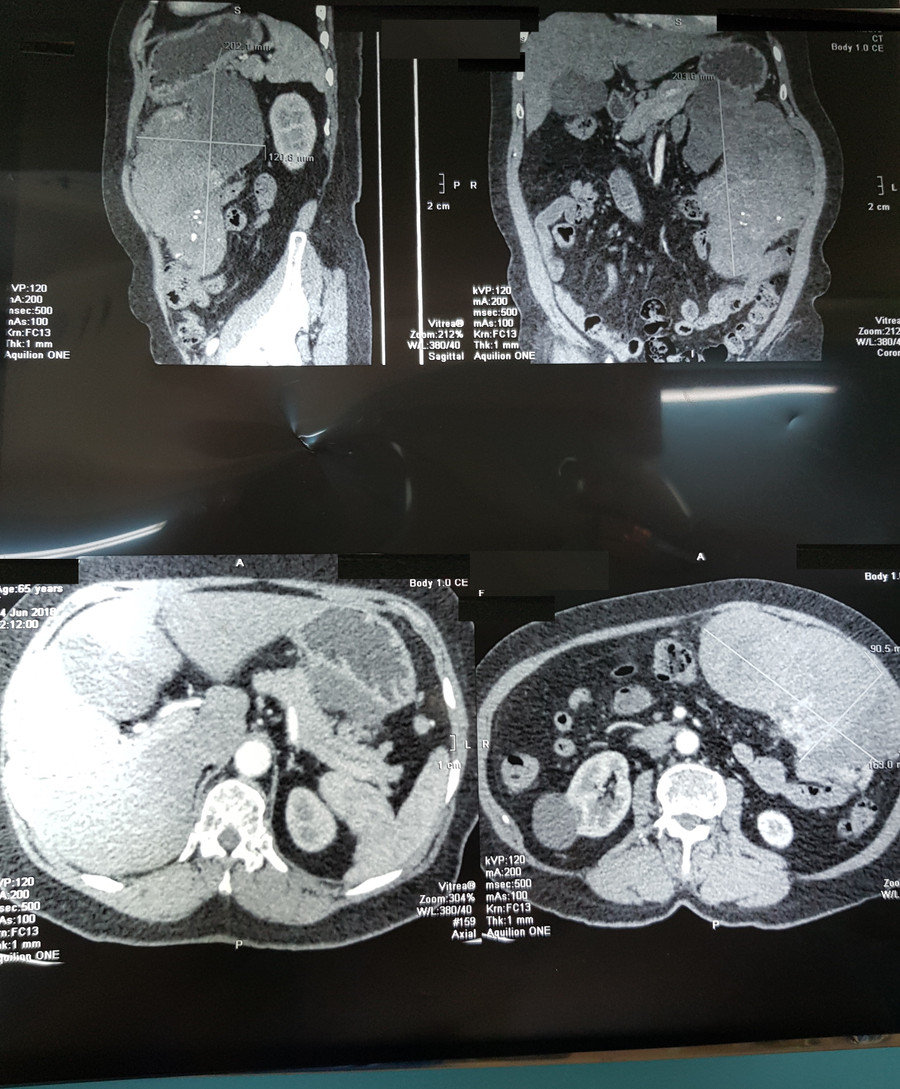

Bên cạnh đó, kết quả CT scan khảo sát vùng bụng phát hiện khối u mô đệm thành dạ dày, choán chỗ toàn bộ vùng hạ sườn trái, có đường kính lớn nhất lên tới 20 cm. Để khẳng định chẩn đoán, bà L. được chuyển đến BV Bình Dân TPHCM để nội soi dạ dày-tá tràng, kết quả cho thấy một khối u dưới niêm mạc dạ dày dạng u mô đệm đường tiêu hóa (GIST-Gastrointestinal Stromal Tumor).

| CT- scan hình ảnh khối u “ khổng lồ” trong ổ bụng của bệnh nhân |

Các bác sĩ khoa Ngoại Tiêu hóa, BV Bình Dân TPHCM, đánh giá đây là một trường hợp khó với khối u có kích thước khổng lồ, lan dính nhiều cơ quan trong ổ bụng và trong tình trạng dọa vỡ nên quyết định thực hiện phẫu thuật tức thời. Tiếp cận phẫu trường, nhóm các bác sĩ phẫu thuật quan sát trong ổ bụng của người bệnh có máu cũ và khối bướu có cuống khoảng 2 cm trên thành dạ dày, xâm lấn tụy tạng, thành đại tràng ngang và mạc nối lớn.